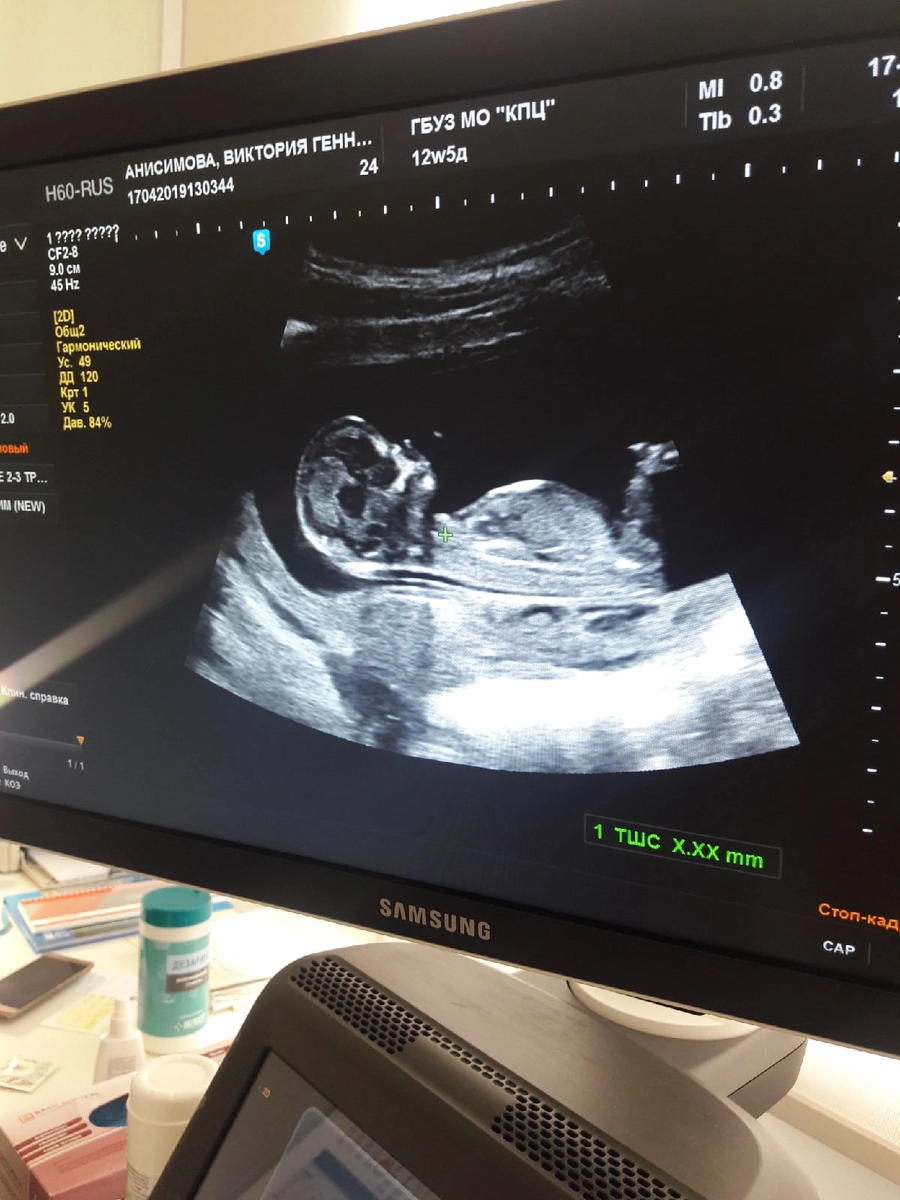

Мальчик или девочка? Врач сообщила пол в 12 недель

Пол мы узнали на удивление на первом скрининге, на сроке 12 недель. Врач спросила, пол говорить ? Я ответила - да. Она уверенно сказала « у вас мальчик»

Я если честно удивилась и переспросила, «вы уверены?» Врач ответила « Да, мальчик»

На самом деле я удивлена что врач на таком маленьком сроке увидела пол и не ошиблась ведь😃